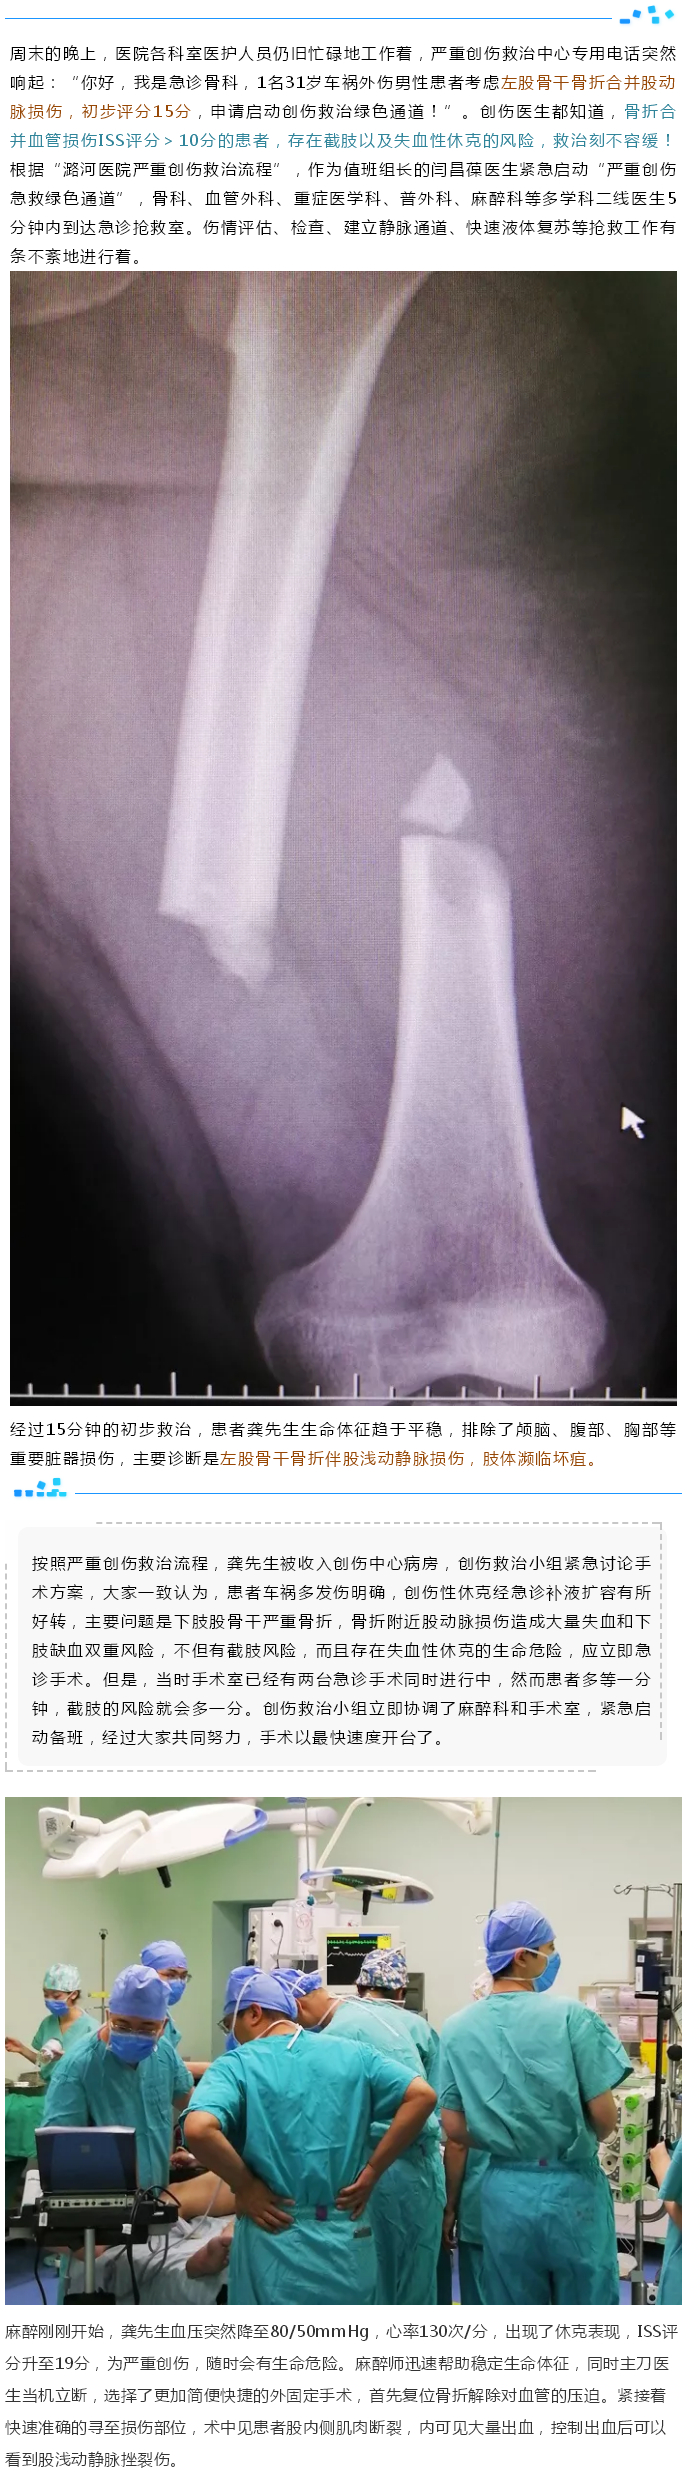

图片新闻